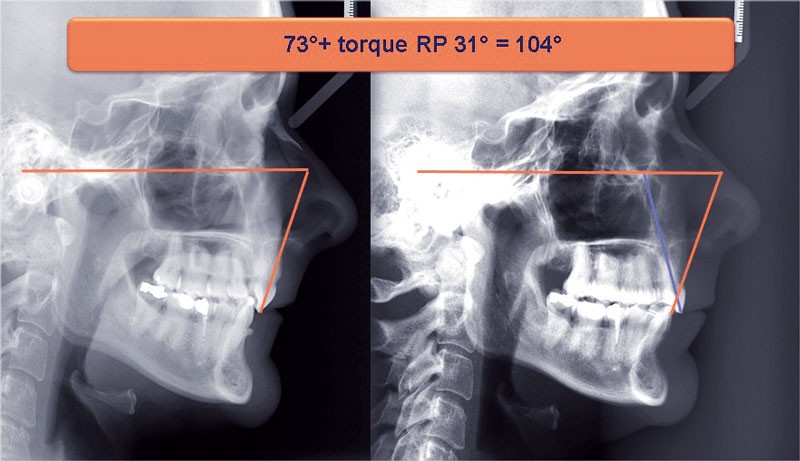

Un appareillage Damon métal a été mis en place, réalisé à partir d’un set up numérique Insignia pour obtenir un contrôle précis des torques et de la forme d’arcade et réduire le temps de finition grâce à un collage indirect très précis.

De larges surélévations postérieures étalées ont été mises en place et la patiente a porté des élastiques précoces suivant les principes de la technique Damon. Les 14 et 24 rempliront le rôle des 13 et 23.

L’objectif, en utilisant la technique Insignia est de réduire le temps de traitement de 28 à 18 mois avec 12 rendez-vous (fig. 5 à 14).